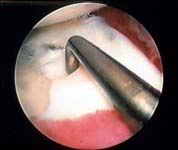

Arthroscopic surgery to remove or repair torn menisci is the definitive treatment for meniscal tears. See Figures 6 and 7.

Surgery is the definitive treatment for torn meniscus. The surgery is done arthroscopically and will include either removal or repair of the torn part of meniscus. Repair can be done only when the tear lies in or just adjacent to the vascular zone of the meniscus.

This minimally invasive surgical treatment involves either removing or repairing the torn segment of meniscus using an arthroscope.